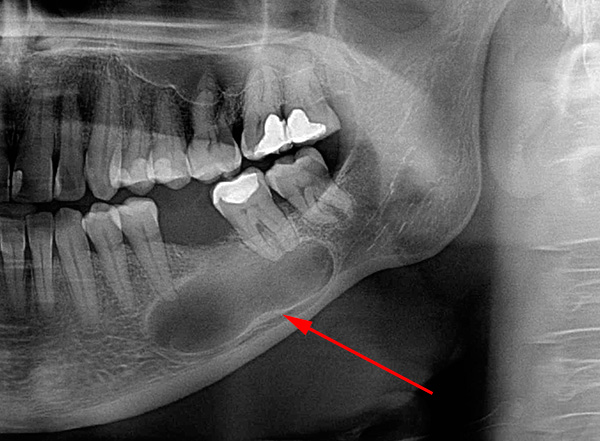

In quasi il 100% di tali casi, si osserva un processo infiammatorio in cima alle radici marce, accompagnato da rarefazione del tessuto osseo, si forma un granuloma o una cisti. In poche parole, nella parte superiore della radice c'è un sacco purulento, che sta solo aspettando che le ali si spezzino con la formazione di un "flusso".

La foto sotto mostra un esempio di denti estratti con cisti alle radici:

- Sullo sfondo di gravi processi infiammatori vicino alla radice (grande cisti, periostite, osteomielite, ascesso, flemmone);

Il peggio di tutto si ottiene nei casi in cui rimane l'apice della radice con un granuloma o una cisti. I problemi sorgono immediatamente sotto forma di infiammazione purulenta sulle gengive ("flusso") o ritardati, ma quasi certamente si verificheranno (possono accadere anche dopo 10 anni). La situazione più spiacevole è quando la radice sinistra viene stretta dalla gomma e si forma un nuovo osso attorno ad essa, cioè il resto del dente si trova in una specie di capsula che la separa dai tessuti sani. Quanto tempo passerà prima che tutto ciò si senta non è importante, ma più tardi seguirà la visita dal dentista, più sarà probabile che con lo sviluppo di una esacerbazione del processo purulento (periostite, osteomielite, ascesso, flemmone) un ospedale sul tavolo operatorio.